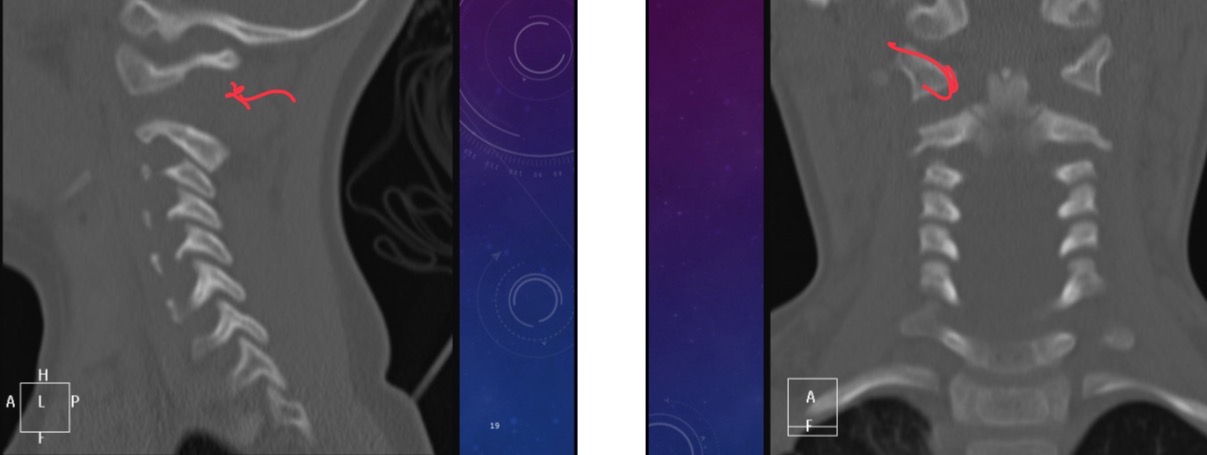

Three-year-old female was in a motor vehicle accident and is in GCS 3. (Coma). What does this cervical spine xr show

Widened interspinous distance between C1/C2

What does chest scan show

Left pneumothorax, atelectasis in right upper and left lower lobes